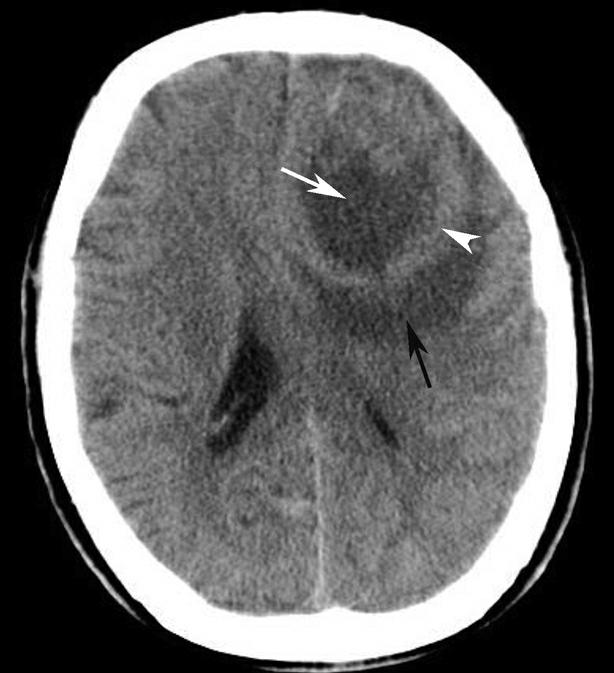

蝶鞍两侧为海绵窦,其内包含颈内动脉及第Ⅲ~Ⅵ对脑神经。海绵窦的密度升高或体积增大常提示病变存在。海绵窦外侧为颞叶,两者之间隔以海绵窦外侧壁。鞍背后方为桥前池及其后方的脑桥,桥前池内可见基底动脉断面,呈圆形稍高密度影。层面中部两侧为颞骨乳突部,其内气化的骨性腔隙为乳突气房。脑桥后方为第四脑室,呈半圆形或新月形,小脑半球的病变(如肿瘤、炎症、出血等)常压迫第四脑室,导致其变形甚至闭塞(图1-2-13)。两侧小脑半球间为小脑蚓部。小脑半球与颞骨乳突部间可见乙状窦。小脑蚓部后方为直窦与上矢状窦汇入窦汇处,窦汇两侧为横窦。静脉窦血栓时可见上述静脉窦增宽、密度明显升高(图1-2-14)。

图1-2-13 第四脑室变形(小脑转移瘤)

A.第四脑室受压变形右移(白箭),提示左侧小脑半球病变;B.左侧小脑半球环形强化结节(黑箭),为瘤体,其周围伴有低密度水肿区